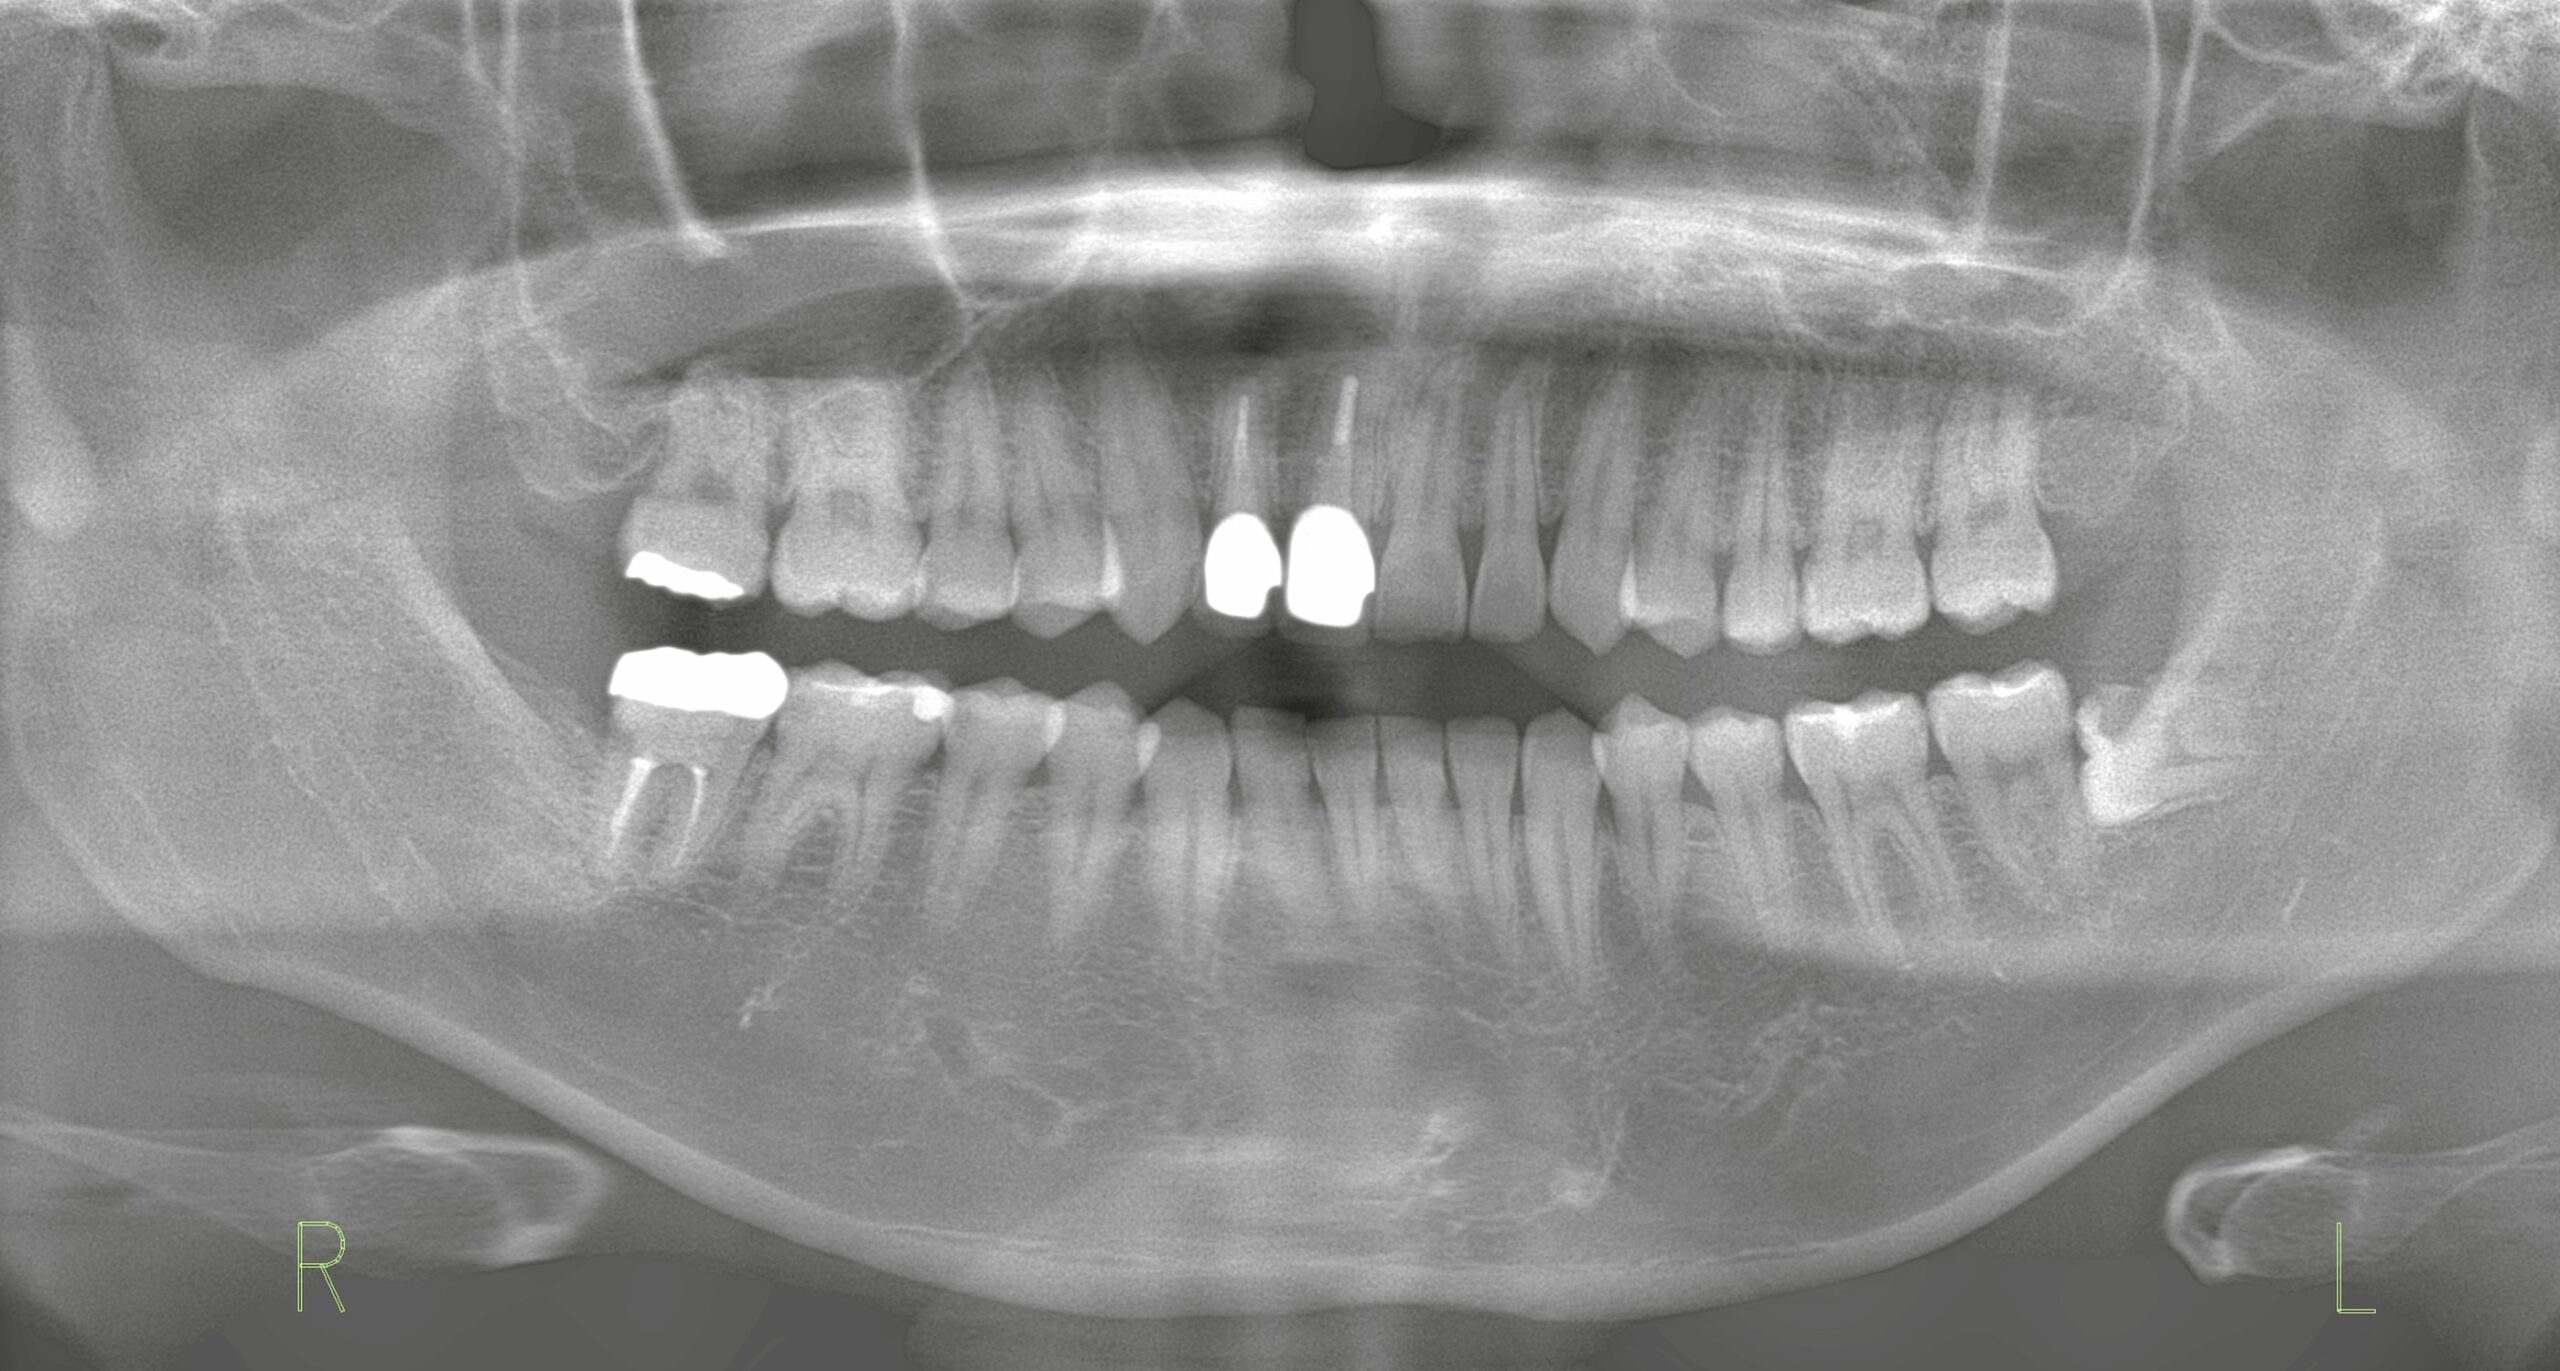

患者さまは右上の前歯が破折してしまい、腫脹と排膿。保存が困難な状態でした。

CT撮影により精査したところ、唇側の骨(前側の骨)が大きく欠損していることが確認されました。前歯は見た目にも大きく影響するため、できるだけ早く、そして審美性を保ちながら治療を進める必要があります。